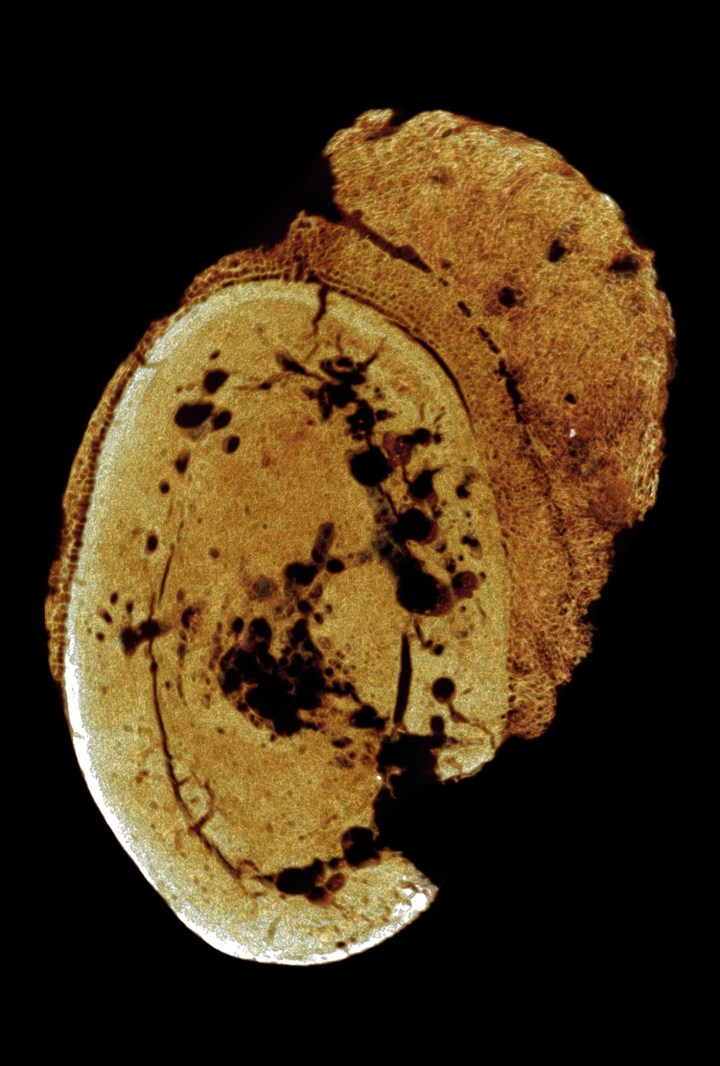

Il cancro rilevato su un osso del piede (University of Witwatersrand)

Un osso del piede, datato tra gli 1,8 e 1,6 milioni di anni fa, contiene una traccia incontrovertibile di cancro (un tumore maligno), e dunque spinge indietro nel tempo la data più antica di questa malattia. L’osso proviene dal sito sudafricano di Swartkrans, all’interno dell’area nota come la Culla dell’umanità. Sebbene non si sappia esattamente quale fosse la specie di questo individuo, era chiaramente un hominine, ovvero faceva parte della tribù che raggruppa uomo, scimpanzé e altri antichi parenti quali Australopithecus.

Il cancro in un osso del metatarso del piede (SK 7923) è stato identificato come un osteosarcoma, una forma aggressiva di cancro che di solito colpisce gli individui più giovani e, se non trattata, porta solitamente a una morte precoce. «A causa della sua conservazione, non sappiamo se quel piede appartenga a un adulto o a un bambino, né se il cancro portò alla morte dell’individuo. Possiamo però dire che ciò avrebbe colpito l’abilità di camminare o correre», dice Bernhard Zipfel, scienziato specializzato nella locomozione degli antichi parenti dell’uomo. «In breve, sarebbe stato doloroso».